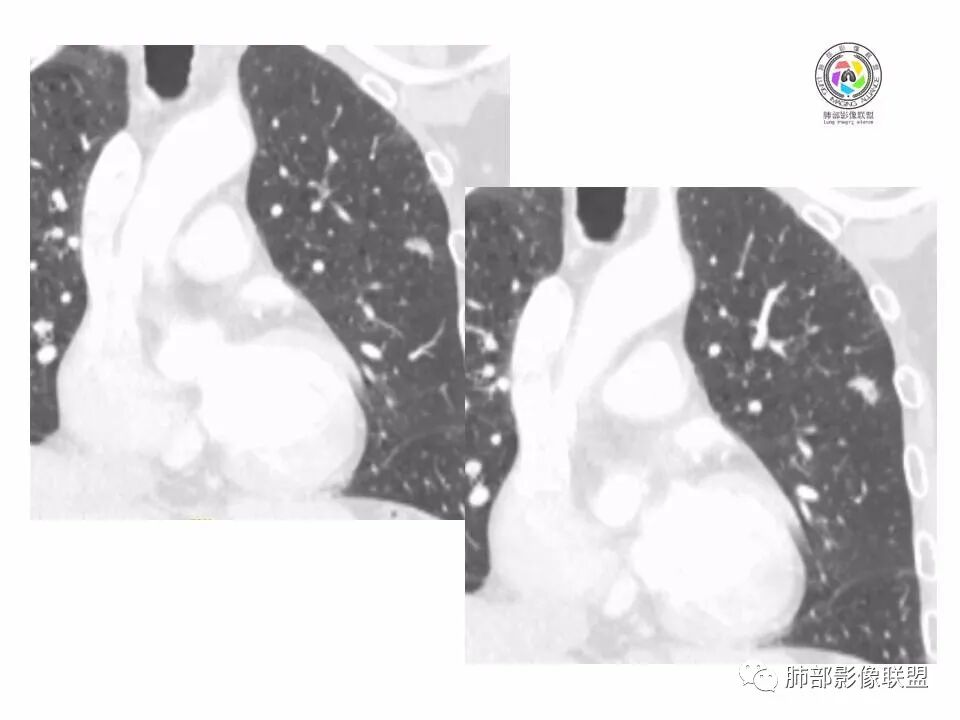

左肺上叶小结节,边缘毛糙,血管集束,支气管截断,强化较明显,但U型凹陷,部分边缘平直,总体感觉恶性大于良性,首选腺癌,鉴别炎性肉芽肿。

左上肺结节,月牙征,边缘纠集有收缩力,小空泡,血管增粗进入,纵隔淋巴结增大,考虑恶性,隐球菌待排。

老年男性,左上肺结节,边缘毛糙,临近血管进入增粗,内部隐约可见小空泡或远端扩张支气管,血管集束并伴月牙铲,有个横断界面看似像脐凹征,常规考虑腺癌,鉴别隐球。

结节,分叶,边缘毛糙,小空泡,血管集束并伴月牙铲,有强化,老年男性,考虑腺癌,建议复查除外结核。

左肺上叶混合密度结节,边缘见边缘清楚磨玻璃,分叶,U型凹陷,首先考虑腺癌。

左肺上叶结节影,边缘可见分叶,血管集束及月牙铲征,病灶内见小空泡影,考虑腺癌可能。

结节密度不均匀,混合磨玻璃结节,大部分实性部分,边缘清,月牙铲征,肿瘤微血管征,考虑肺癌。

老年男性,体检发现左肺上叶结节,周围浅分叶伴磨玻璃影,有血管相连,U型凹陷,纵隔见肿大淋巴结,考虑为恶性,腺癌可能。

左肺形态不规则结节,边缘收缩,毛刺,有月牙铲,纵隔窗比肺窗小,不密实,近段血管与病灶相连,强化不明显,老年男性,综合考虑,恶性,腺癌,鉴别炎性结节。建议穿刺。

老年男性,左肺上叶结节,边界清,不规则,有毛刺,血管集束,空泡,边缘有气肿带,考虑腺癌,鉴别肉芽肿。

左肺上叶小结节,边缘毛糙,血管集束,支气管截断,有月牙铲,首选腺癌,鉴别炎性肉芽肿。

左上肺实性小结节,短毛刺,月牙铲,似见小空泡,血管集束,有轻度强化,首先考虑腺癌。

老年男性,肺气肿背景,左肺上叶小结节,大部分边缘平直,部分边缘膨隆,局部可见月牙铲,边缘少许磨玻璃,边界清晰,血管进入,轻度强化,首先考虑腺癌,常规抗炎后复查,除外炎性结节。

左上肺结节,短毛刺,空泡,月牙铲,脐凹征,考虑腺癌。

左肺上叶混合密度结节,边界清,分叶,毛刺,血管进入,月牙铲,有强化,首先考虑腺癌,有平直边,收缩力不明显,常规先抗炎。

左上肺结节分叶,边缘毛糙,小空泡可能,血管集束,月牙,纵隔窗面积小于肺窗,有磨玻璃成份,有强化,老年男性,白细胞高,恶性的征象都有,但磨玻璃的形态和边界不好评估,实性为主,看形态和边缘局部较散缺乏饱满感,顶着压力反着来猜炎性可能大。复查不消失会考虑腺癌或黏液腺癌。

老年男性,肺气肿背景,左肺上叶实性结节,边界清,边缘平直为主,细长毛刺,较明显强化,考虑炎性病灶,隐球?

老年男性,左肺上叶结节,边缘可见长毛刺、较软,并可见分叶,周围可见清楚磨玻璃密度,内可见空泡征,增强后呈均匀强化,良恶性征象都有,感觉收缩力不强,化验白细胞偏高,建议抗炎治疗后复查除外腺癌。

老年男性,左肺上叶混合密度结节,空泡,分叶,血管集束,有强化,考虑腺癌;细长软毛刺,血管走行自然,边缘有平直收缩,白细胞高,肿标正常,考虑炎性结节。猜炎性结节,鉴别腺癌。

左肺上叶前段mGGN,边缘见毛刺及月牙铲,考虑腺癌,需要薄层图像确认所见征象。

左肺上叶结节,分叶,边缘毛糙,小空泡,月牙铲,有强化,考虑浸润性腺癌,鉴别炎性肉芽肿。

患者老年男性,体检发现。查癌胚抗原不高。血常规血象升高。胸部CT:肺气肿背景,左肺上叶近胸膜下实性结节,边缘光滑,边界清楚,可见毛刺、血管集束、月牙铲征象,增强不明显,内可见低密度区,综合考虑恶性病变,腺癌可能大,鉴别结核及炎性结节。

老年男性,左肺上叶结节,周围浅分叶伴磨玻璃影,有血管相连,月牙铲。纵隔见肿大淋巴结,但白细胞高。腺癌首先,需排除炎性假瘤。抗炎治疗后复查。

老年男性,体检发现左肺结节,分叶、脐凹、月牙铲及月牙铲附近有边缘清楚的磨玻璃影,上述征像均指向恶性肿瘤,有疑问的地方:毛刺软无力,无胸膜牵拉及白细胞计数升高。整体是腺癌,需要抗议后复查以排除炎性病变。

图片有限,左肺上叶结节病灶,有张力,有收缩及小泡征,边缘可见月牙征,周围长毛刺及血管集束征,增强目测有中度以上强化,首先考虑恶性病变,腺癌。

左肺上叶前段小结节,边缘稍毛糙,月牙铲,血管进入可疑脐凹征,小空泡?增强有强化,老年男性,要高度警惕腺癌,但感觉毛刺偏细软,周围磨玻璃不明显,常规查隐球菌荚膜抗原除外隐球菌,血象高,抗炎后短期复查除外炎性结节。

左肺上叶mGGN,边缘收缩平直为主,肺窗显示清楚,纵隔窗体积缩小,未见胸膜牵拉,倾向感染性结节,隔期复查。